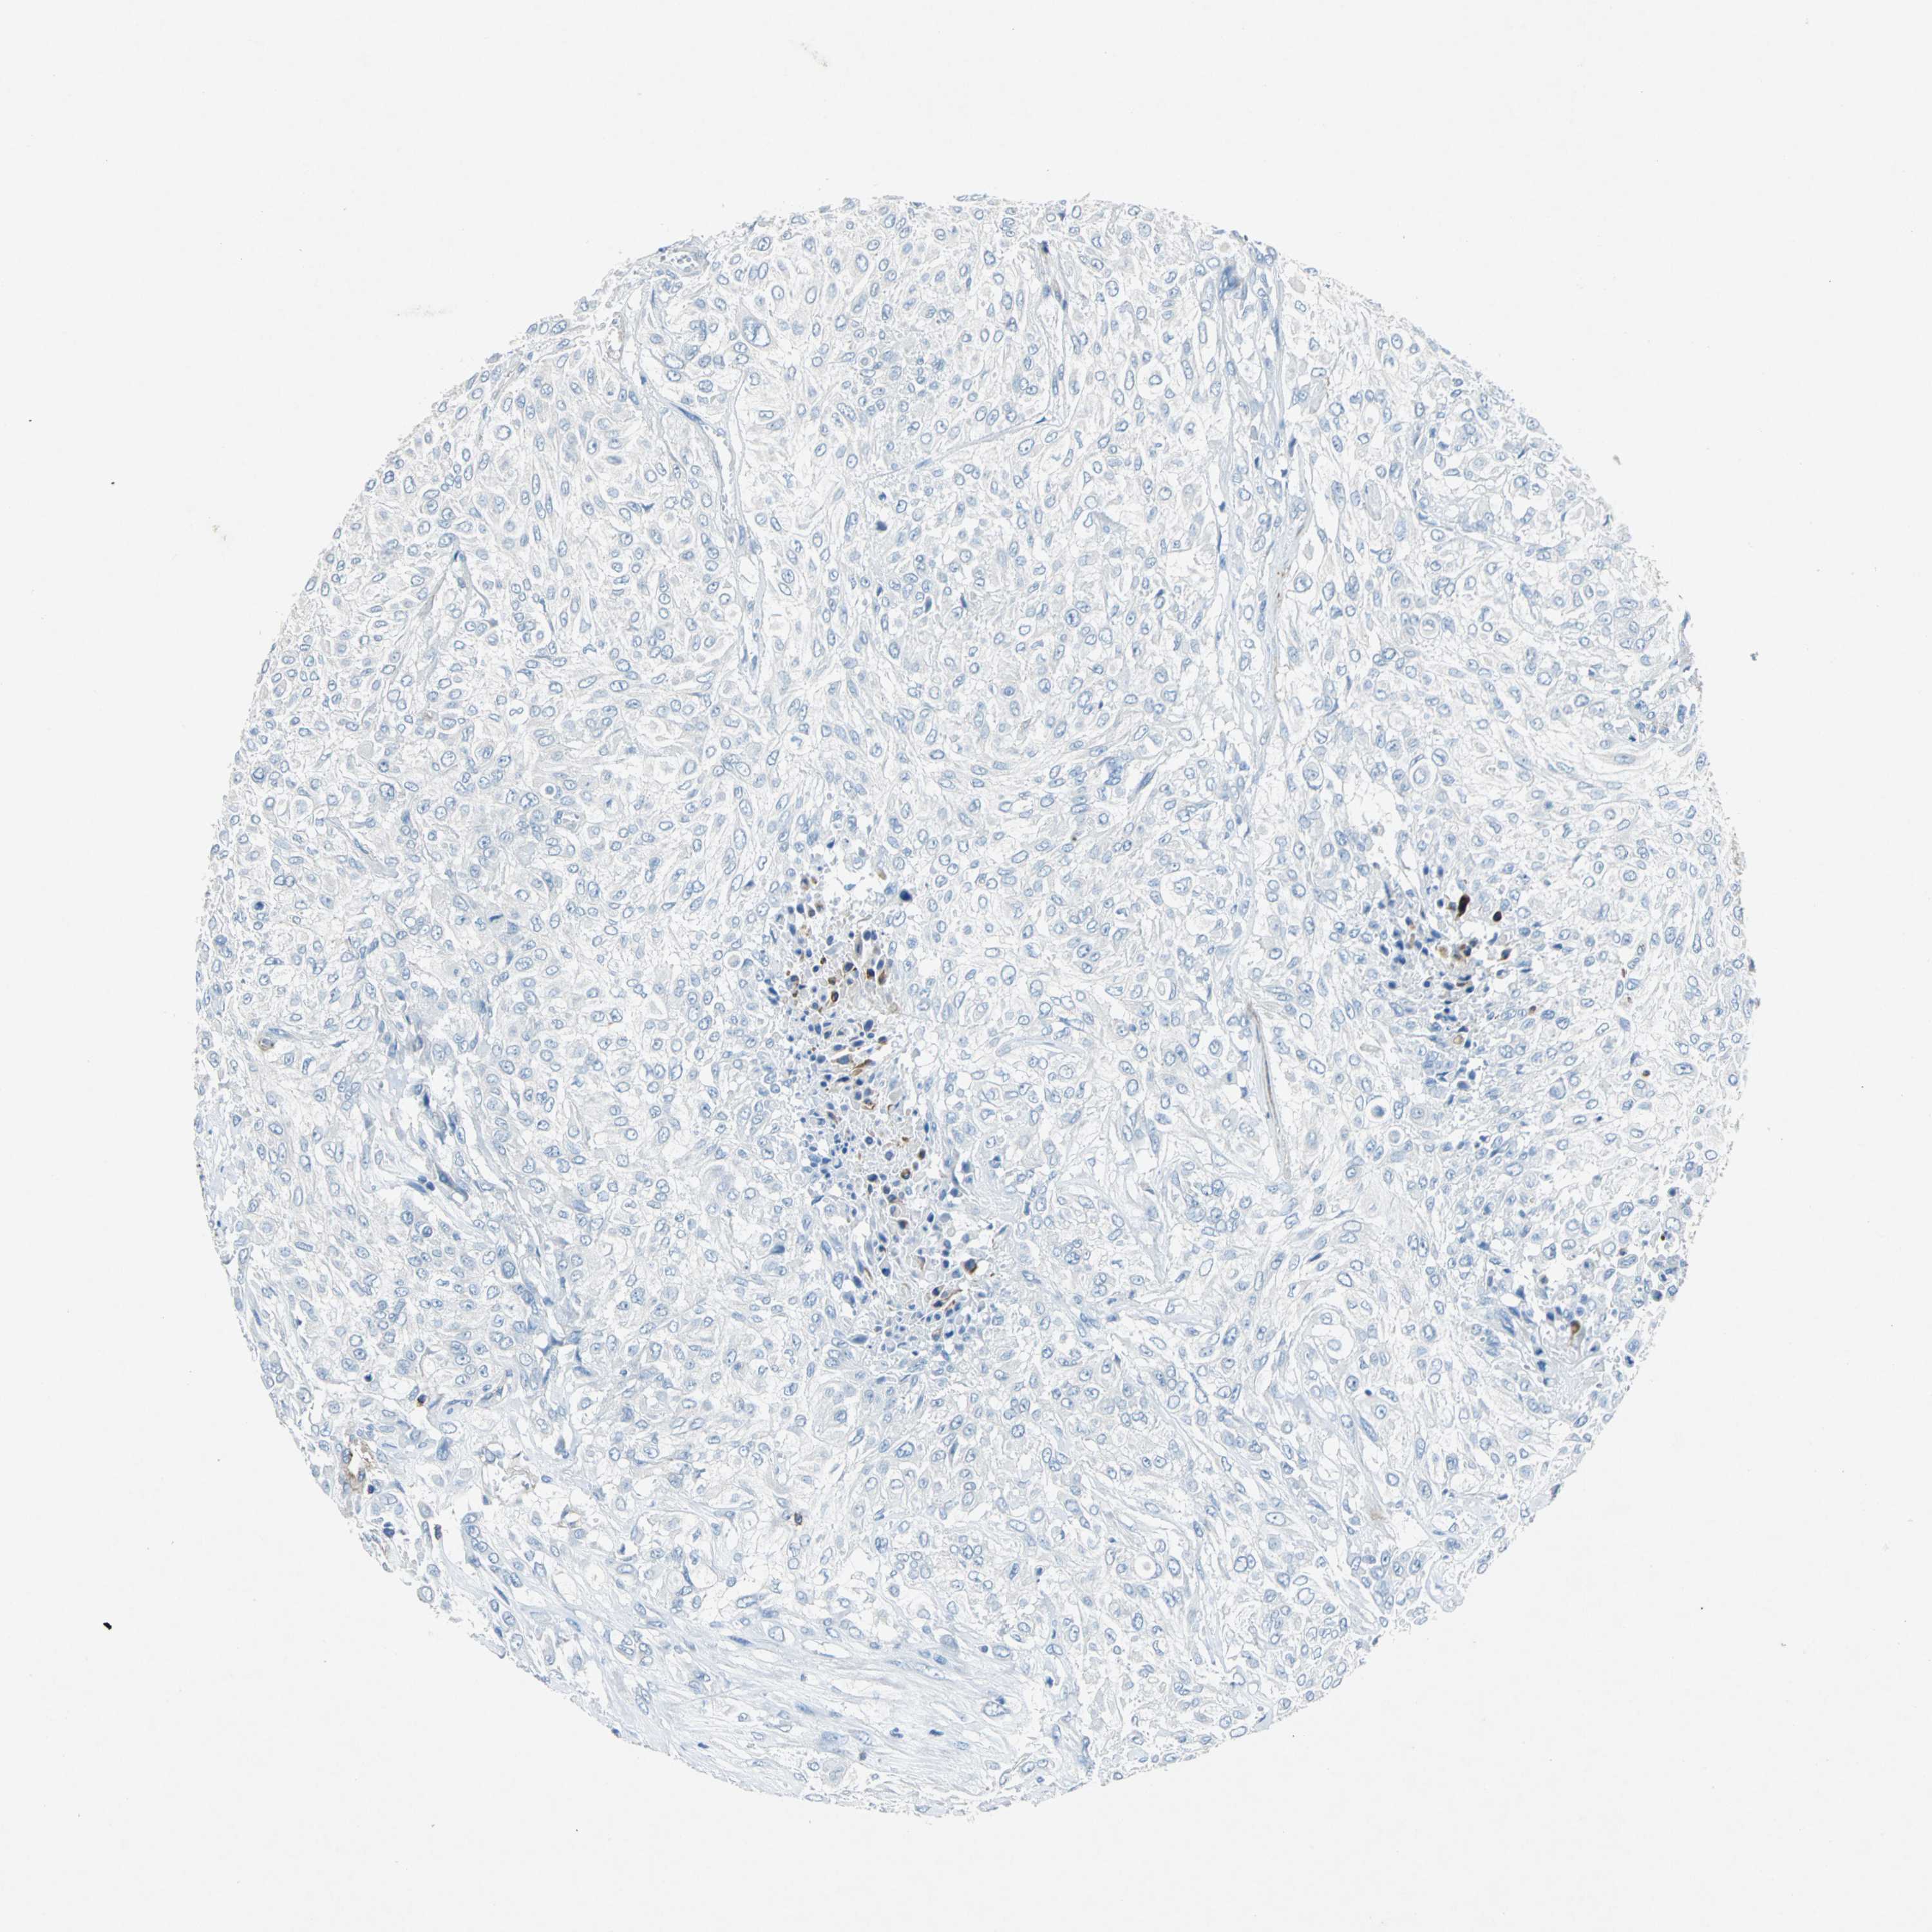

UROTHELIAL CANCER - Protein expressioni

A mouse-over function shows sample information and annotation data. Click on an image to view it in a full screen mode. Samples can be filtered based on level of antibody staining by selecting one or several of the following categories: high, medium, low and not detected. The assay and annotation is described here.

Note that samples used for immunohistochemistry by the Human Protein Atlas do not correspond to samples in the TCGA dataset.

Antibody stainingi

Antibody staining in the annotated cell types in the current human tissue is reported as not detected, low, medium, or high, based on conventional immunohistochemistry profiling in selected tissues. This score is based on the combination of the staining intensity and fraction of stained cells.

Each image is clickable and will lead to virtual microscopy that enables deeper exploration of all samples and also displays staining intensity scores, fraction scores and subcellular localization as well as patient and tissue information for each sample.

Antibody HPA005985

Urothelial carcinoma, High grade

Urothelial carcinoma, Low grade